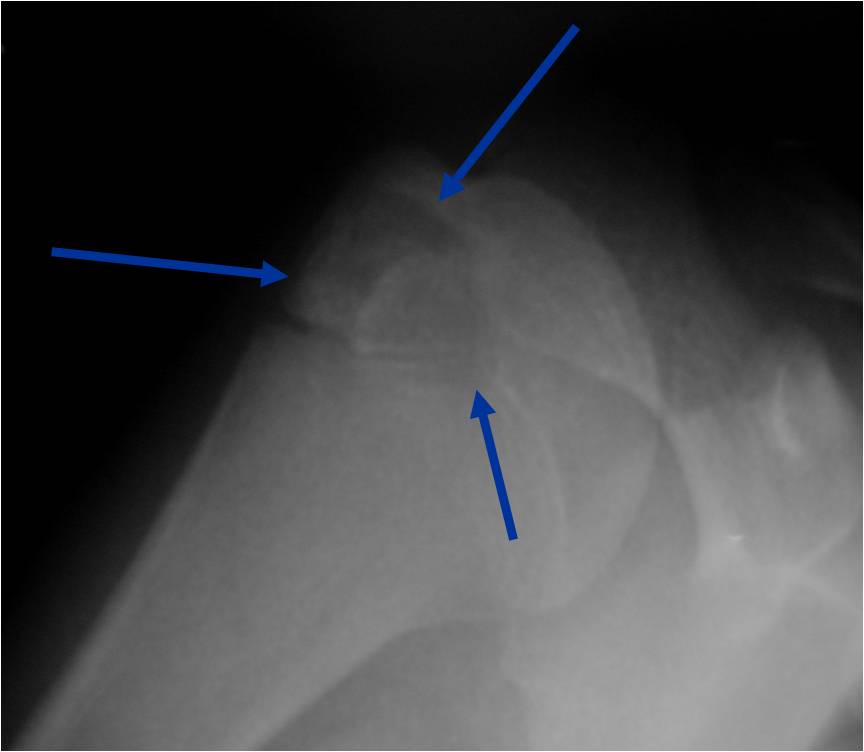

Radiographic Presentation

- Presents as a highly defined/well circumscribed geographic oval/round lytic defect

- Surrounded by rim of sclerotic bone

- Usually in epiphyseal region

- Lesion ranges from 3 cm to 6 cm diameter

- Usually radiolucent

- May have fine trabeculae and irregular calcifications

- Calcifications are often better detected with a CT scan but are not uniformly present

- Lesions may expand the bone and new periosteal bone may form

- Bony end plate, cortex, bone contour are unaffected

Plain x-ray appearance:

- Geographic lytic lesion IA/IB margin of sclerosis

- Usually Eccentric more often than Central in the bone

- Rarely expansile (rarely penetrates the cortex)

- Calcified chondroid matrix 30%-50% of cases

- Often better detected with a CT Scan

- Periosteal Reaction 30-50% of cases

- Usually occurs in Adjacent Diaphysis/Metaphysis since epiphysis is intraarticular and not surrounded by periosteum